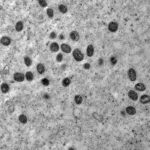

A produção servirá para imunização de crianças com idade entre 3 e 5 anos, que foi o último grupo a ser incluído no Programa Nacional de Imunização contra a covid-19.

Até o momento, a CoronaVac é a única vacina autorizada para essa faixa etária. A recomendação foi feita pelo ministério em 15 de julho e foram usadas as doses já existentes nos estoques dos estados e municípios para este público.